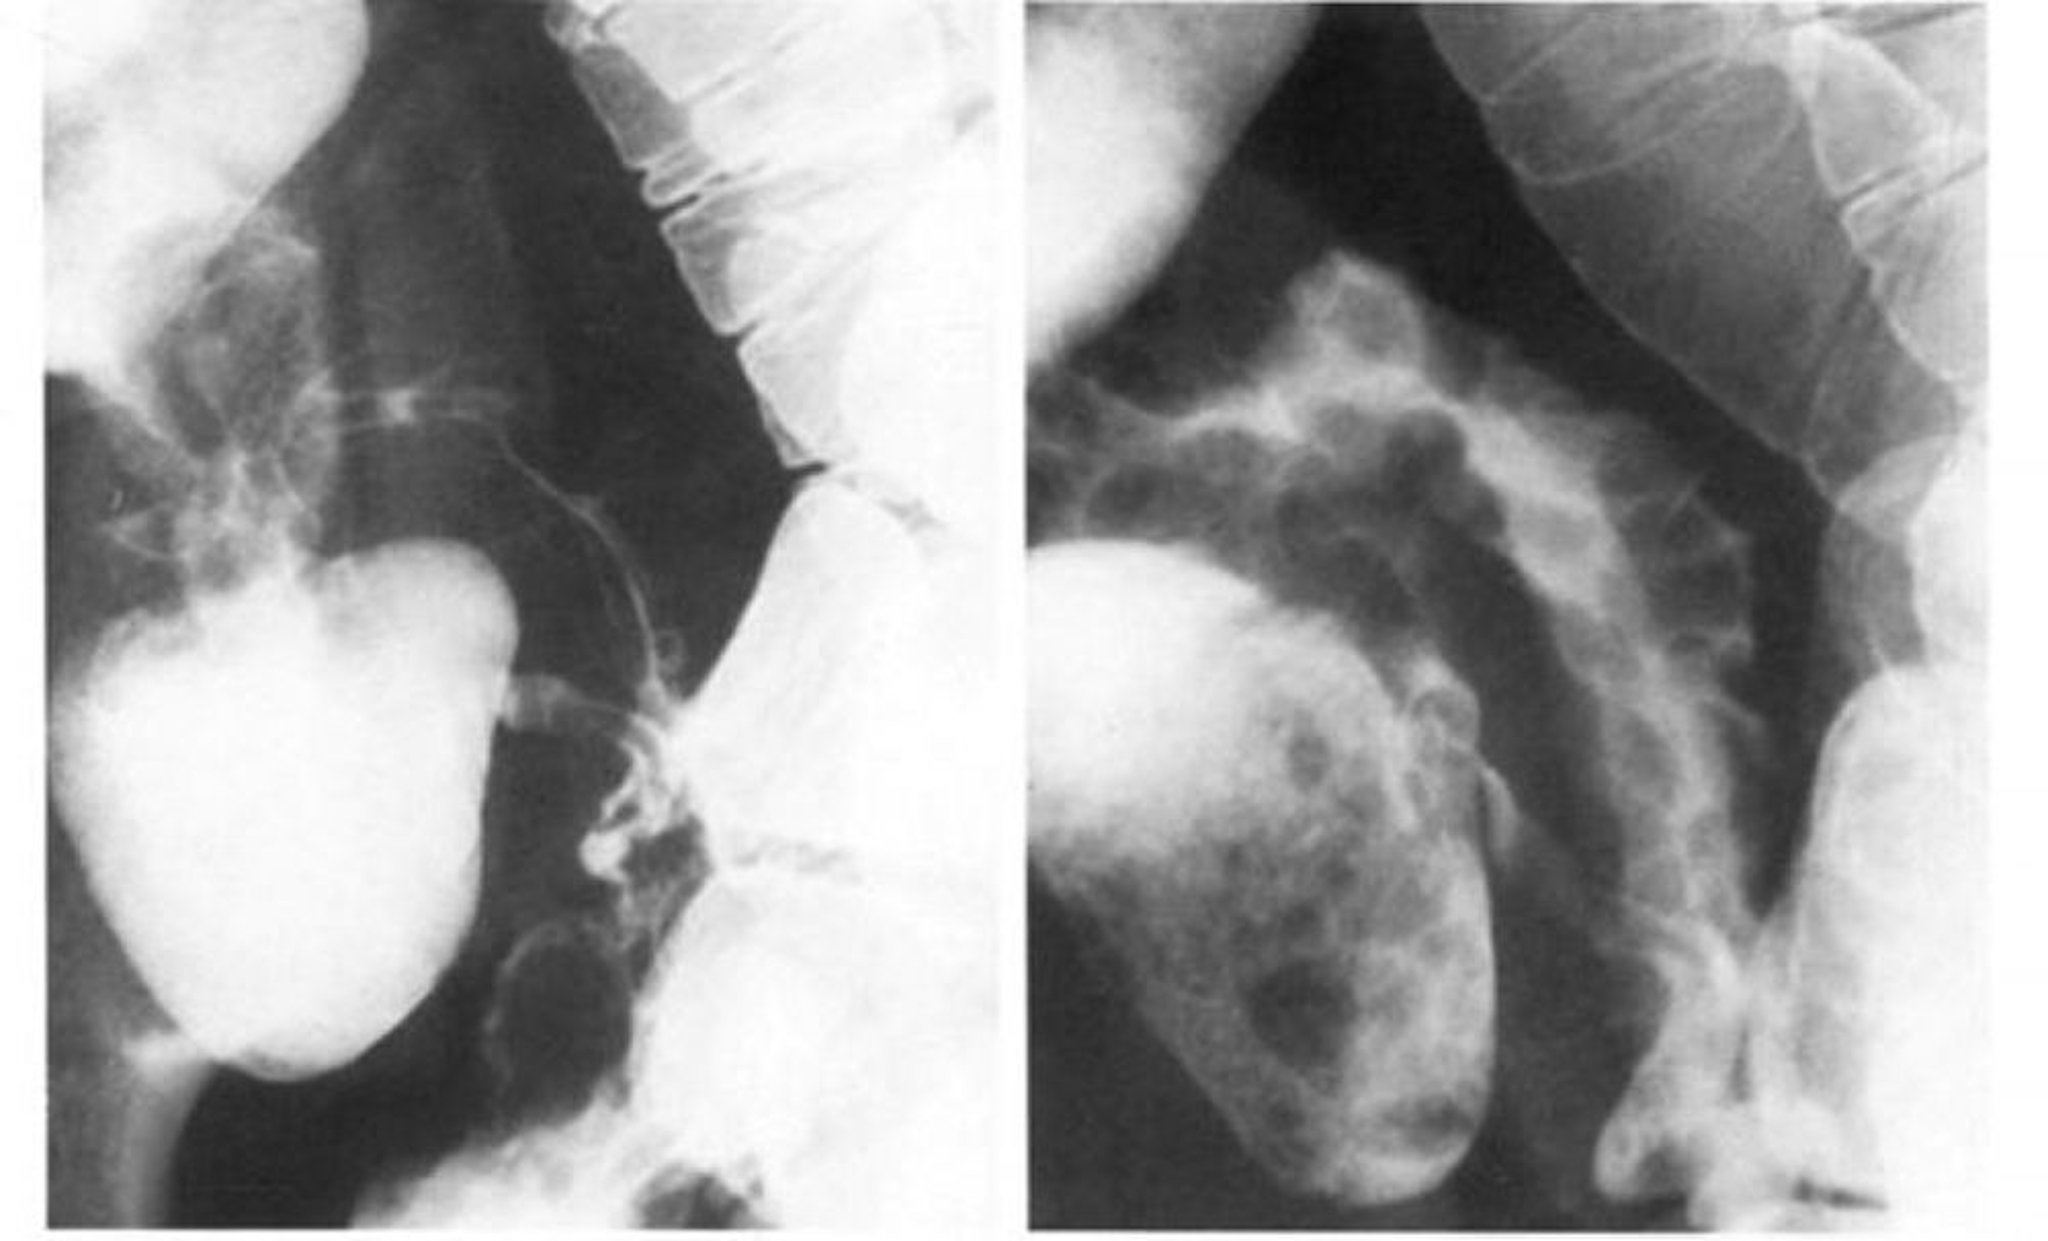

Transito dell'intestino tenue nel morbo di Crohn che mostra il segno del nastro

L'immagine a sinistra mostra che lo spasmo cancella il modello a ciottoli dell'ileo terminale, che si osserva meglio in doppio contrasto nell'immagine a destra.